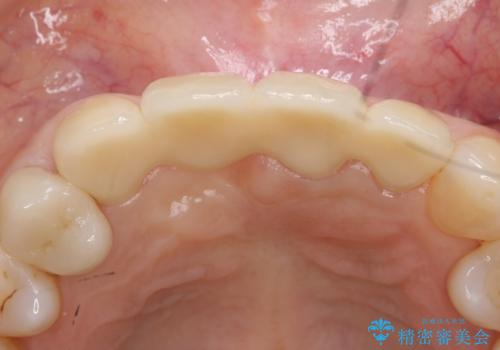

抜歯後、骨と歯肉の回復を待ち、オールセラミッククラウンによるブリッジで補綴を行いました。

オールセラミッククラウンについて

今回用いたオールセラミッククラウンはジルコニアフレームという白い素材の上にセラミックを盛っているため、審美性が非常に高いのが特徴です。

また、ジルコニアは人工ダイヤモンドの材料にも使われているほど高い強度を持っており、そのためオールセラミッククラウンは審美性だけでなく、奥歯やブリッジの補綴も可能とするクラウンです。